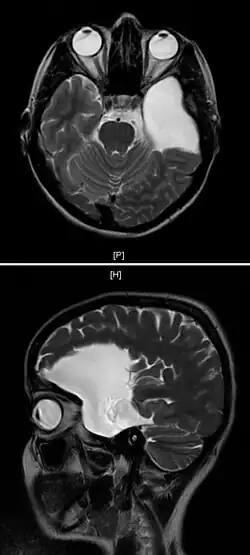

| An MRI of a 25-year-old woman with left frontotemporal arachnoid cyst. | |

Arachnoid cysts are cerebrospinal fluid covered by arachnoidal cells and collagen[1] that may develop between the surface of the brain and the cranial base or on the arachnoid membrane, one of the three meningeal layers that cover the brain and the spinal cord.[2] Primary arachnoid cysts are a congenital disorder whereas secondary arachnoid cysts are the result of head injury or trauma.[3] Most cases of primary cysts begin during infancy; however, onset may be delayed until adolescence.[2]

Diagnosis

Diagnosis is principally by MRI. Frequently, arachnoid cysts are incidental findings on MRI scans performed for other clinical reasons. In practice, diagnosis of symptomatic arachnoid cysts requires symptoms to be present, and many with the disorder never develop symptoms.